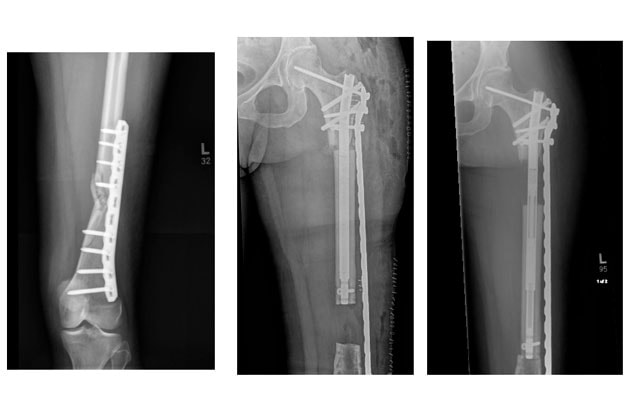

Deformity correction, lengthening Deformity correction, lengthening

Femur with intramedullary nail: bone deformity correction and lengthening.

Internal bone transport Internal bone transport

Femur with intramedullary nail and plate: internal bone transport.